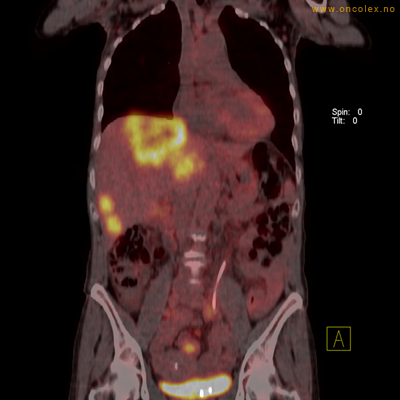

Vev som tar opp mer radioaktivt stoff, synes som hvite områder som lyser opp mer i forhold til annet vev som tar opp mindre sukker.

Spredningssvulster til lever med sentral nekrose.